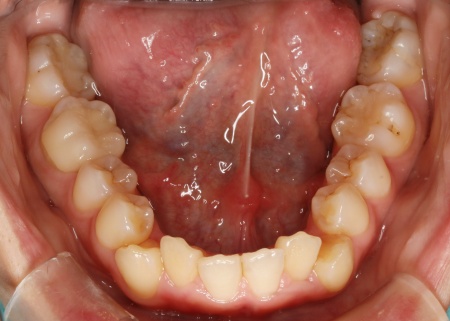

20代女性 ワイヤー矯正とマウスピース矯正を併用したハイブリッド矯正で歯並びを改善した症例

拝見したところ、上下の歯が正しく並ぶためのスペースが足りず、デコボコに生えていました。

とくに、犬歯が正しい歯並びから大きく飛び出した位置に生えており、いわゆる八重歯の状態です。

また、奥歯を噛み合わせた際に上下前歯が噛み合わず隙間ができる開咬(かいこう)も認められました。

以上のことから、歯並びを改善するための矯正治療が必要だと診断しました。